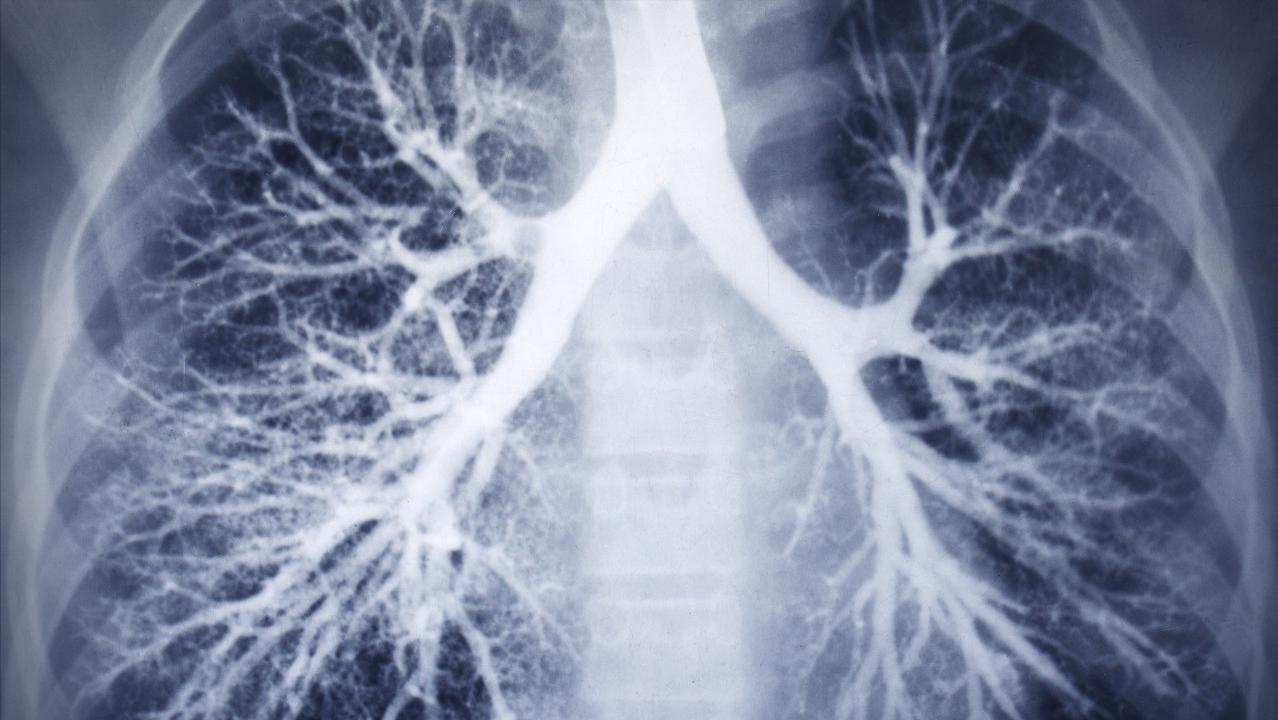

我点开手机上同学发的照片,仔细看了一看。胸片上显示老爷子双肺的确有很多自肺门向外延伸得像树枝一样的阴影,密密麻麻的。为了进一步明确肺纹理增多的原因,我告诉同学明天把老爷子带到医院,我再好好给老爷子检查检查。

肺纹理是放射科的一个专业术语,是指胸部影像检查时所看到的从肺门向肺周围延伸的放射条状阴影。这种呈放射条状,像大树一样的阴影主要由我们刚刚说的肺动脉、肺静脉、支气管及淋巴管这些组织组成的。

肺纹理增多,在胸部影响检查下,发现从肺门到肺野外围延伸的这些呈放射状,像树枝一样的阴影正常人,有时增加。